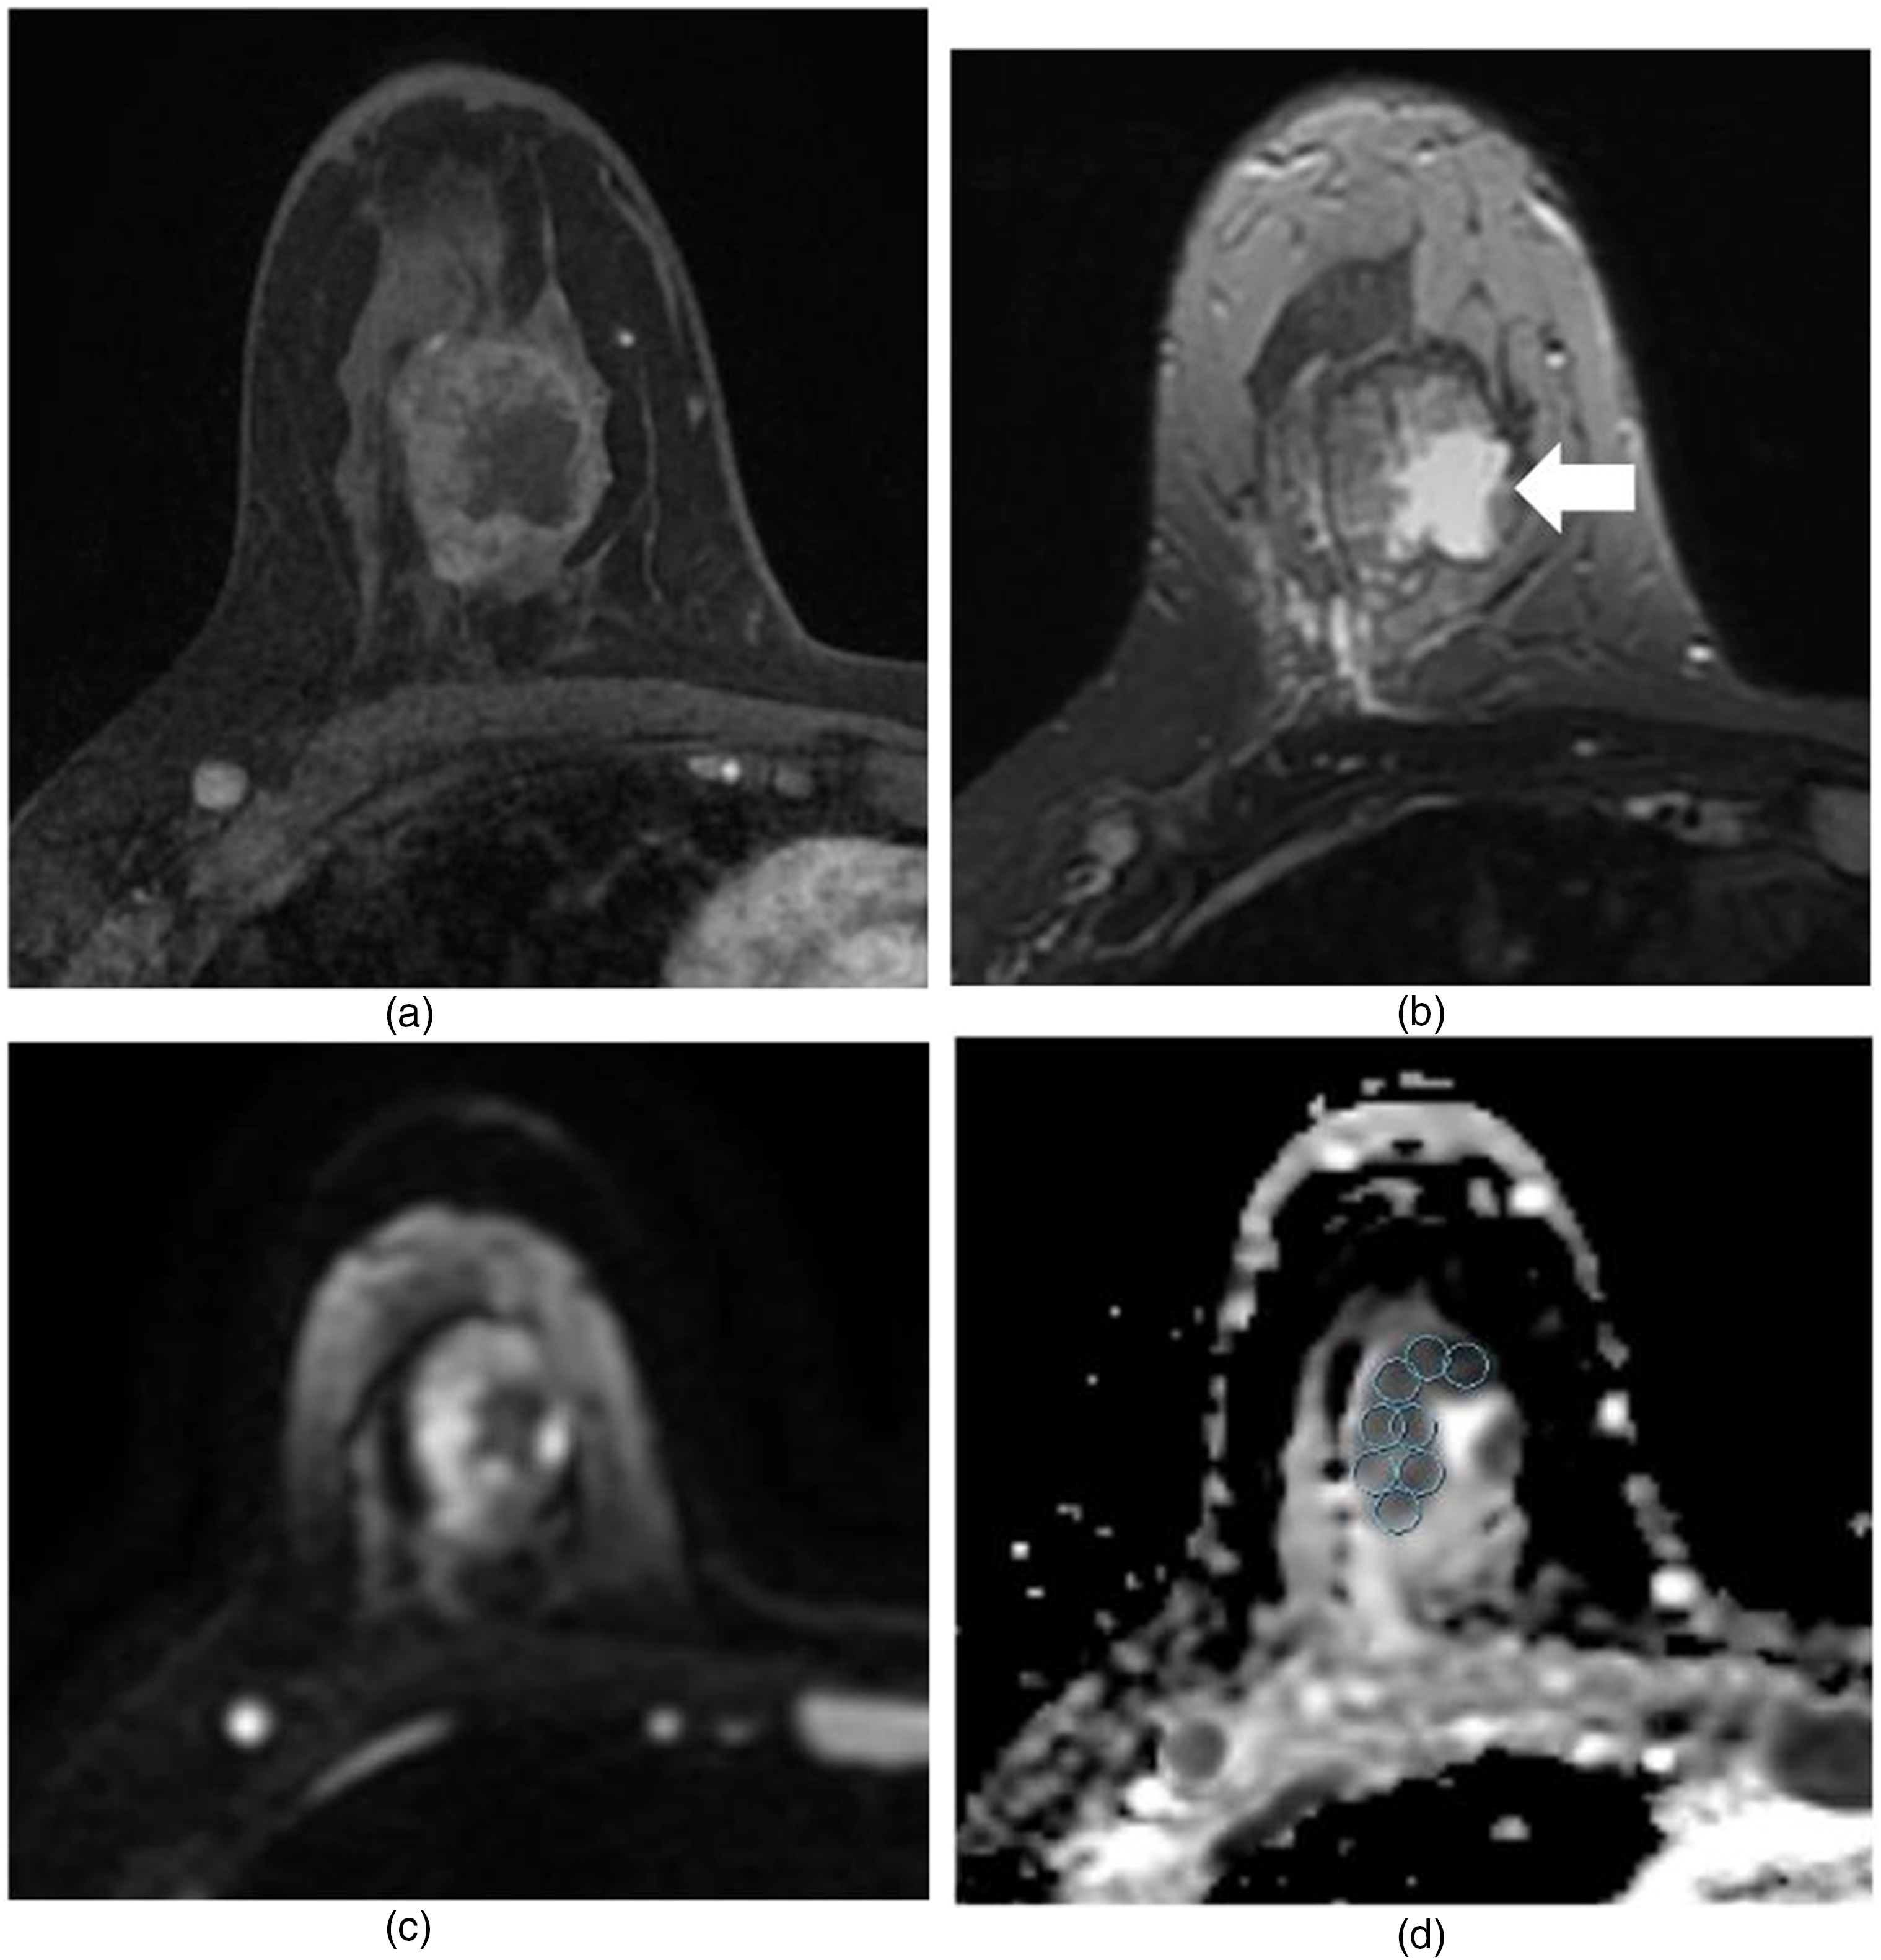

MR images in a 43-year-old-woman who underwent X (NAC) for invasive ductal carcinoma, and who experienced a pathologic complete response. (a) and (b) Pre-NAC transverse contrast-enhanced T1-weighted (a) and T2-weighted (b) images. In (a), heterogeneous enhancing mass with a maximal diameter of 3.4 cm is noted. In (b), there is a central T2 high-signal intensity area in the mass, representing cystic or necrotic area (arrow). (c) and (d) Pre-NAC DWI (c) and ADC map (d). (d) Multiple ROIs of 20.31 mm2 were manually placed within the mass avoiding cystic or necrotic area. Minimum ADC value was 446 × 10−6 mm2/s, and the maximum ADC value was 1182 × 10−6 mm2/s. The calculated ADC difference was 736 × 10−6 mm2/s. After NAC, there was no enhancing mass in Rt. breast at contrast-enhanced MRI, suggesting complete response (not shown). Pathologic result after Rt. breast modified radical mastectomy showed no residual invasive tumor, suggesting complete response.